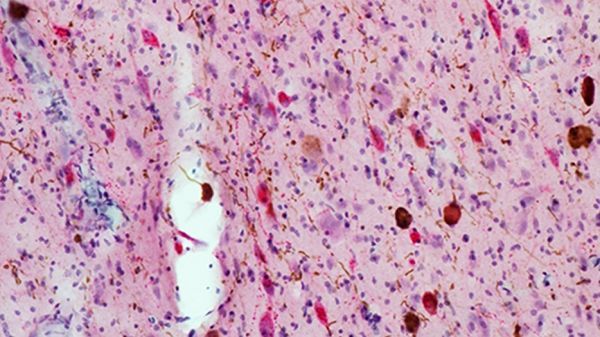

Image: Tissue from Alzheimer’s brains shows increased tau protein buildup (brown spots) and fewer neurons (red) compared to healthy tissue, illustrating how Alzheimer’s pathology drives selective loss of wakefulness promoting neurons in these regions. (Credit: Grinberg lab / UCSF)